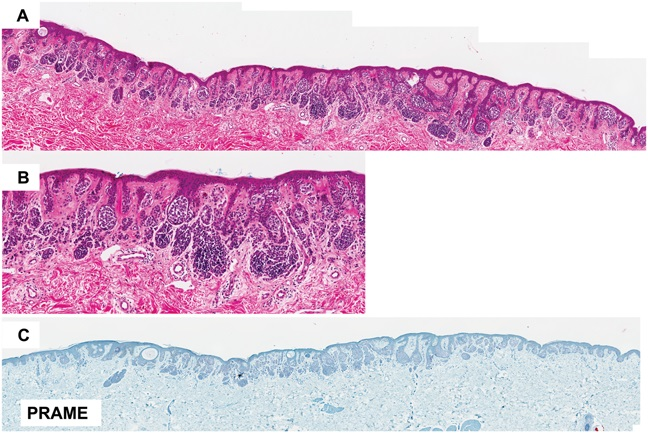

For all the non-believers in. Nested and DN-like melanomas, another data point to help you believe.

#WhatsNewInDermpath Utilizing PRAME expression and a meta-analytic framework for iSALT to explore atypical late-onset nevi of the elderly and their relationship with lentiginous and nested nevoid melanomas https://t.co/fUiHaGbnzV